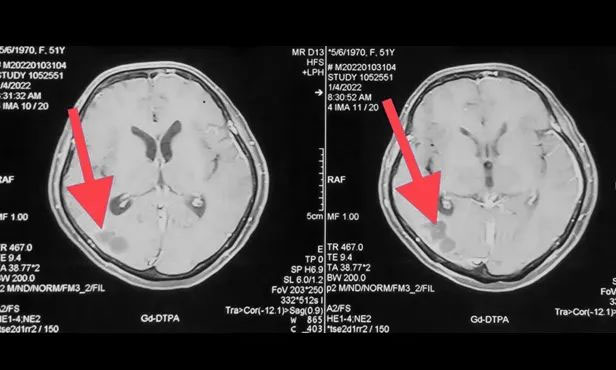

▲ 剛?cè)朐簳r(shí)病灶影像

▲ 完成穿刺,黑色囊液被順利引流

▲ 經(jīng)復(fù)查,病灶較前明顯縮小

按照腫瘤復(fù)查的標(biāo)準(zhǔn),復(fù)查影像顯示王女士顱內(nèi)病灶相較于來院時(shí)明顯縮小。家屬為此特意向陳琦主任致謝,并對(duì)醫(yī)院的治療和服務(wù)表達(dá)了充分肯定。